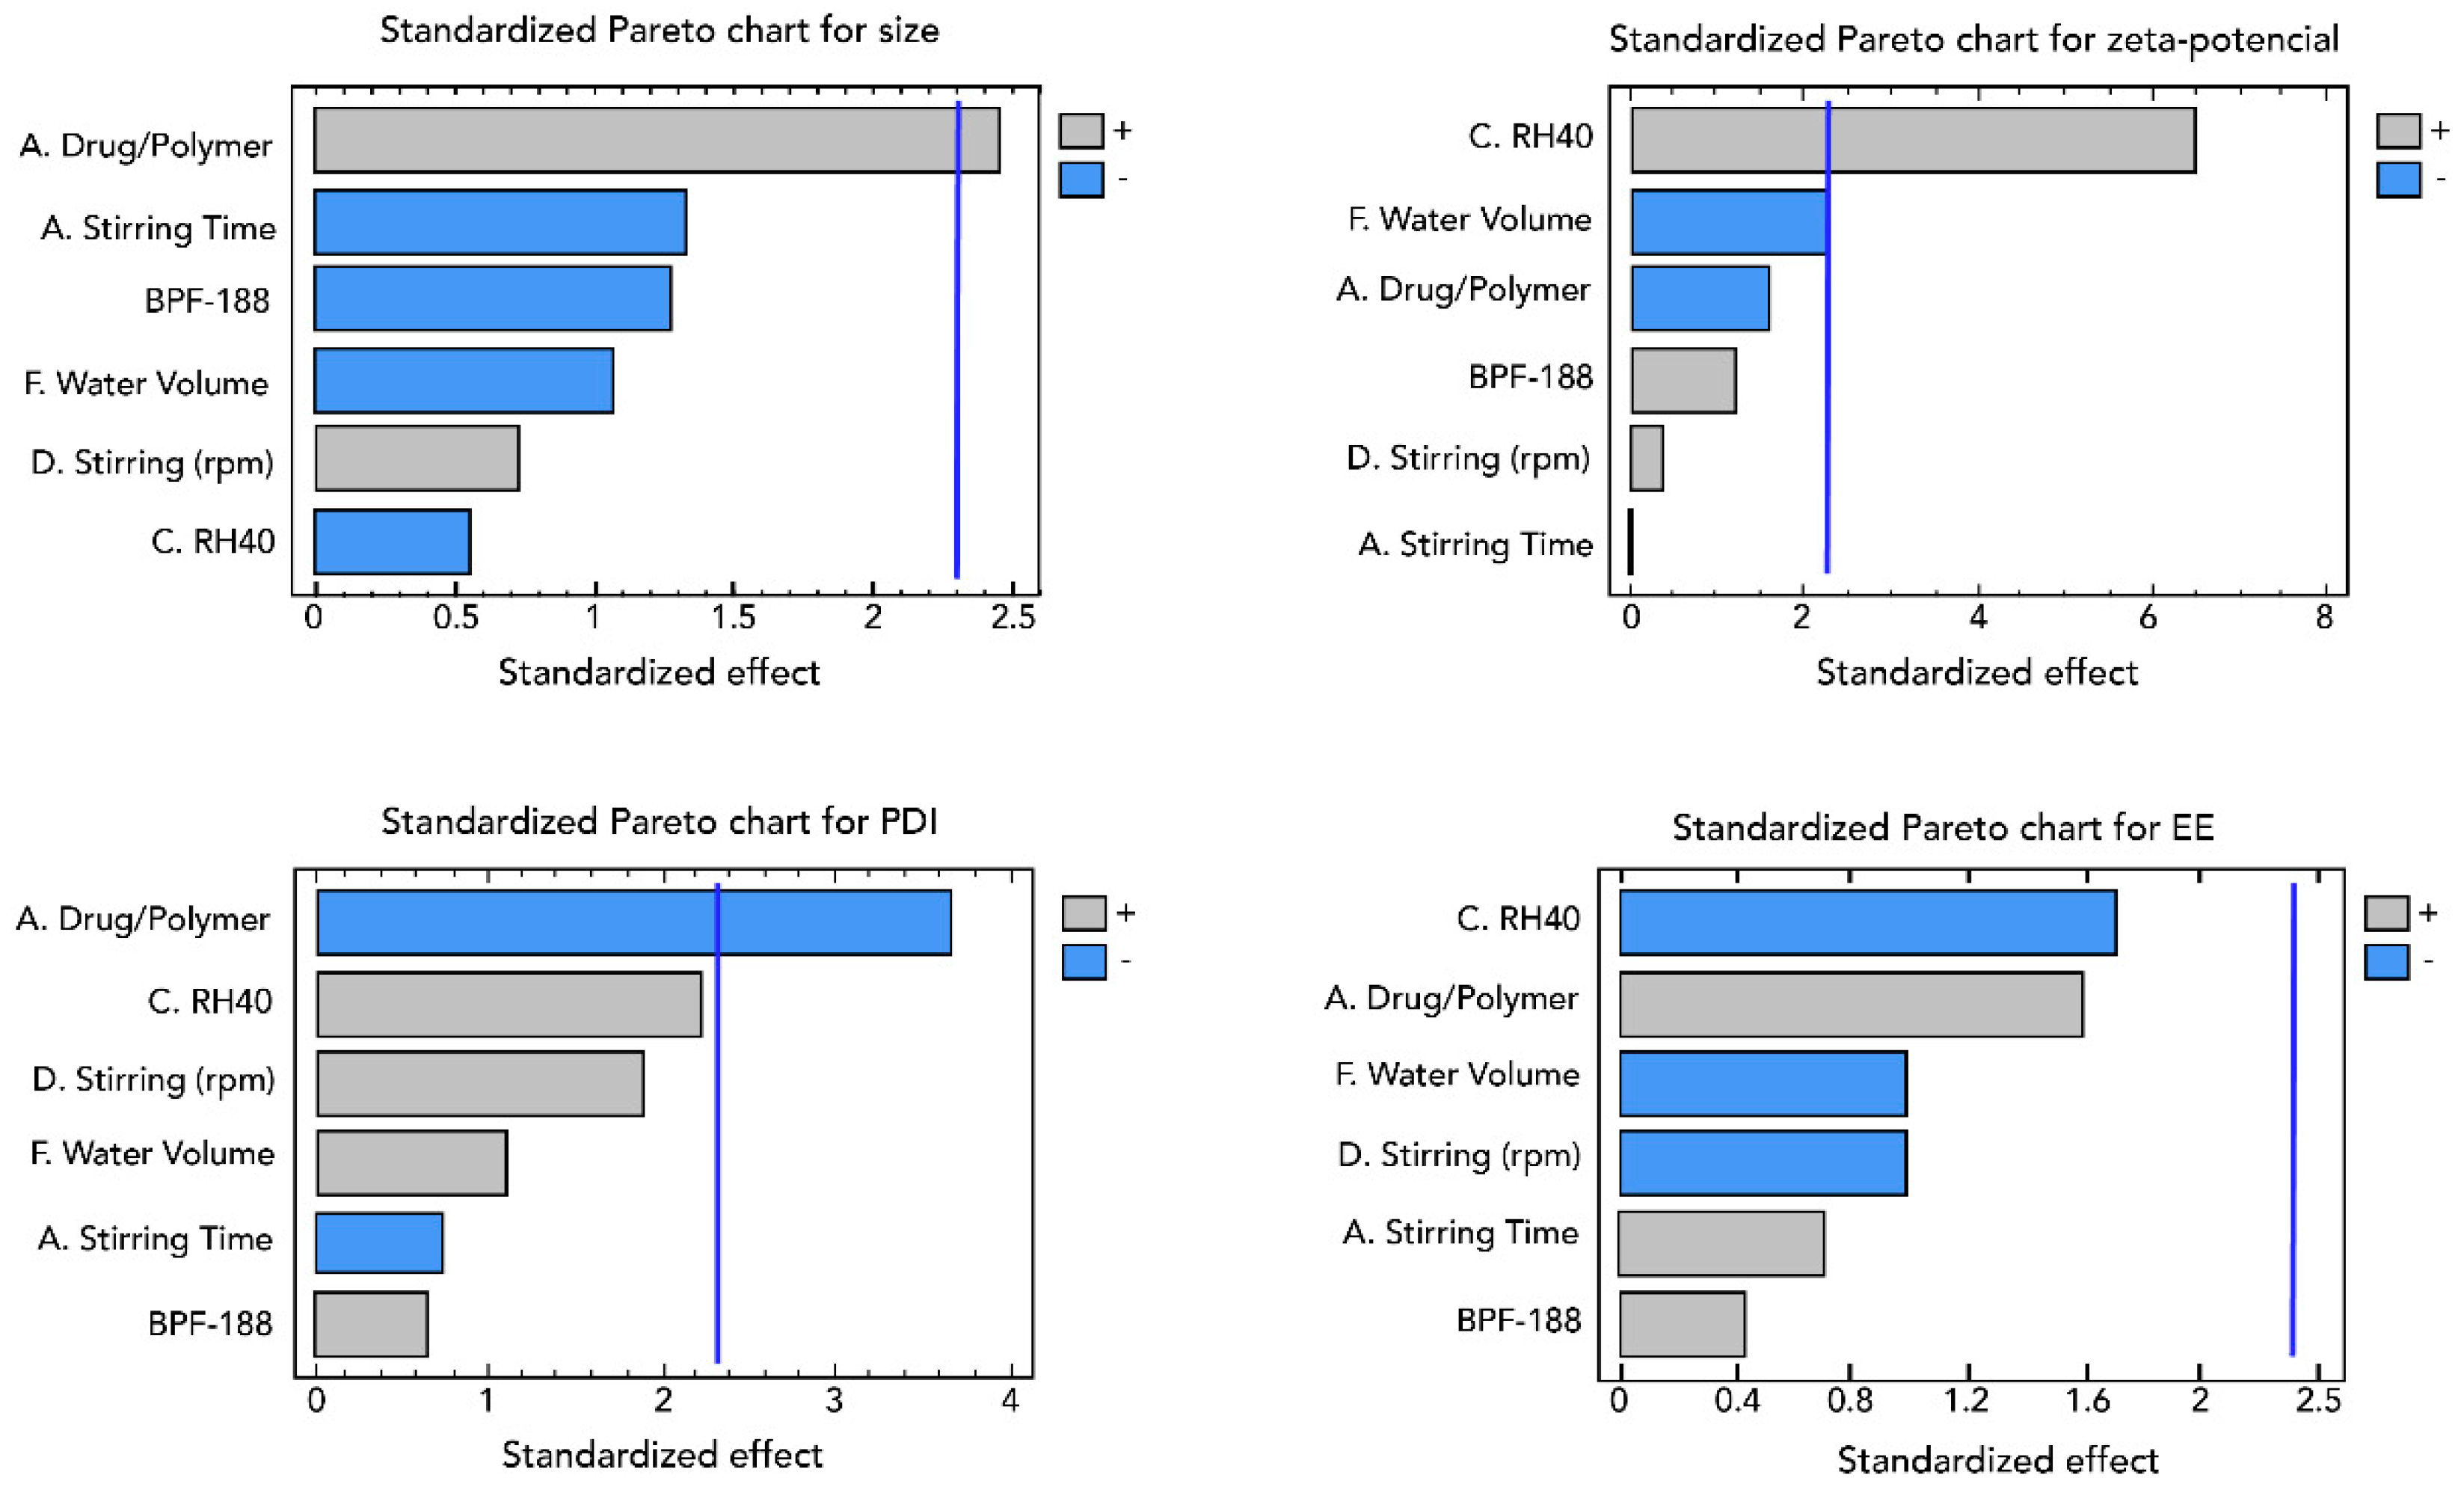

2.5. Design of Experiment (Screening and Optimization)

3.1.1. Screening Design

3.1.2. Optimization of Nanoparticles